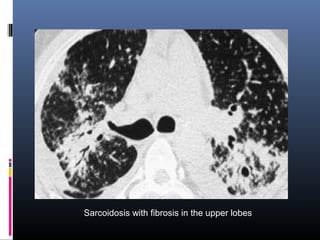

Sarcoidosis with fibrosis in the upper lobes

Sarcoidosis with fibrosisin the upper lobes

• #41 Sarcoidosis with fibrosis in the upper lobes. Typical HRCT findings. stage IV sarcoidosis.; Notice the distribution of the conglomerate masses of fibrosis in the posterior part of the lungs. In addition there are multiple small well-defined nodules. Some of these nodules have the typical sub pleural distribution.